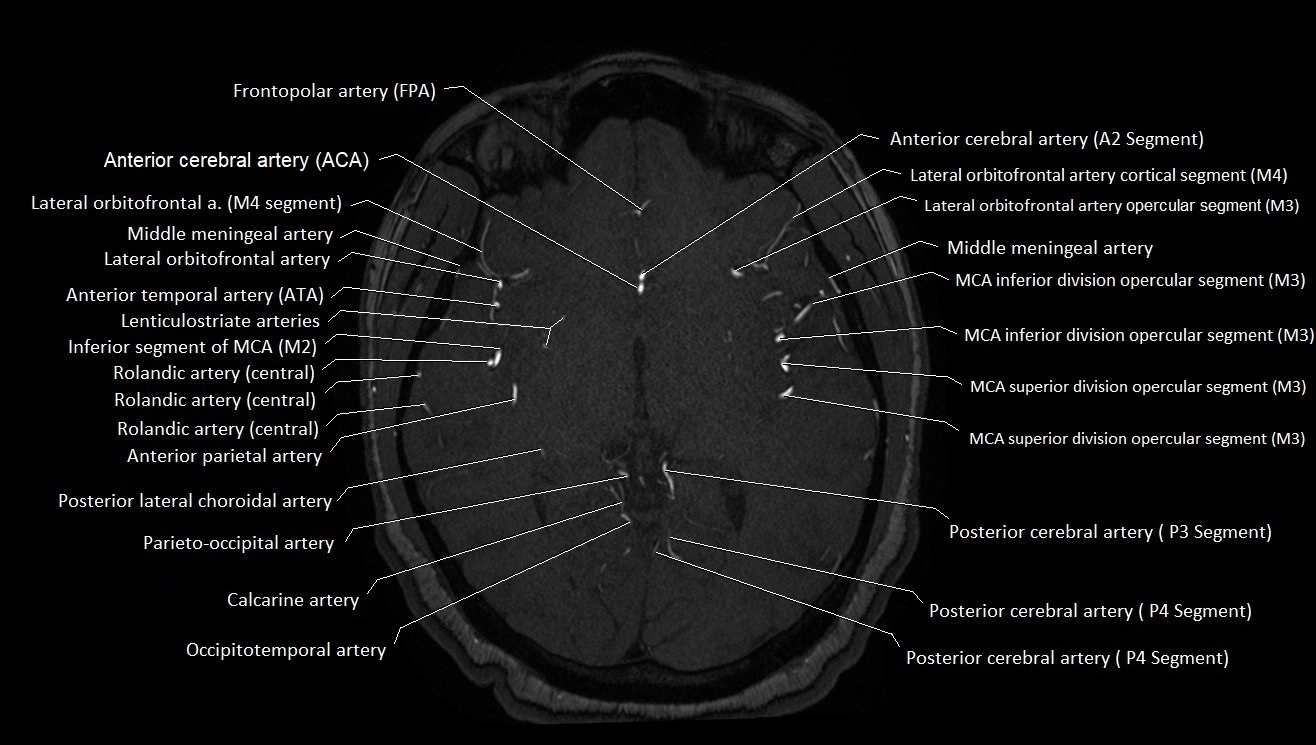

MRI images

image